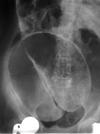

מהו הממצא

פאנקריאטיטיס כרוני